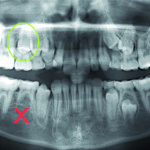

Le cisti del mascellare superiore: diagnosi differenziale tra cisti odontogene e non odontogene

In questo articolo si analizza un caso esemplificativo del trattamento della cisti naso-palatina. Si considereranno eziopatogenesi, sintomi, peculiarità radiografiche, caratteristiche istopatologiche, rapporti anatomici, approccio...